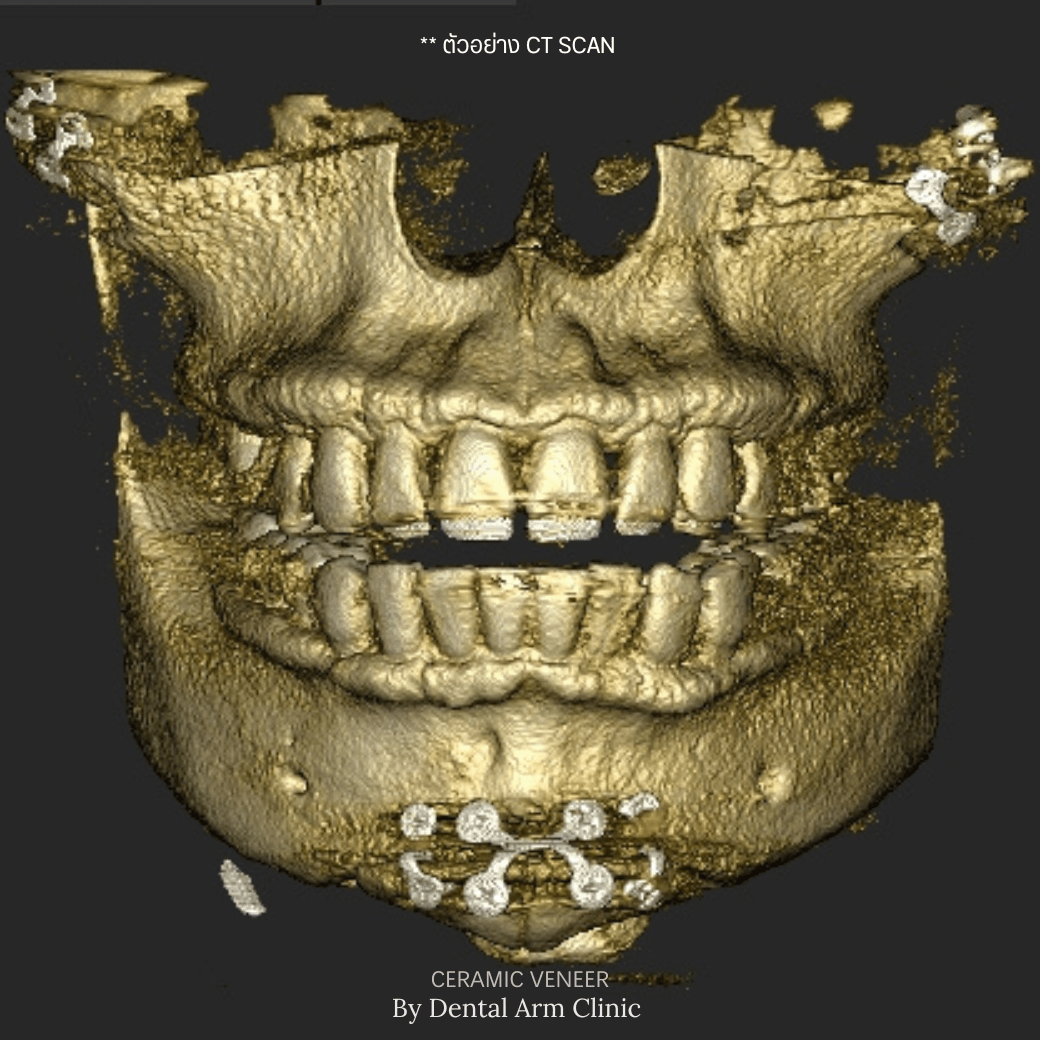

จะเห็นได้ว่าการตัดเหงือกทั้งสองแบบเหมาะกับสภาวะของเหงือกและฟันที่ไม่เหมือนกัน โดยปกติแล้วทางคลินิกจะใช้วิธีการเอ็กซเรย์แบบสามมิติ (CBCT)

เพื่อประเมินลักษณะของเหงือก ฟันและกระดูกรอบบ้าฟัน ว่าจำเป็นจะต้องตัดเหงือกแบบไหน (เป็นวิธีที่แม่นยำและไม่เจ็บตัวเลย) ทั้งนี้แนะนำว่าให้ลองเข้ามาปรึกษากับคุณหมอดูก่อนว่าควรจะทำแบบไหนดีเพื่อที่ให้ได้เหงือกที่สวยที่สุดและอยู่กับเราได้นานที่สุดนะครับ